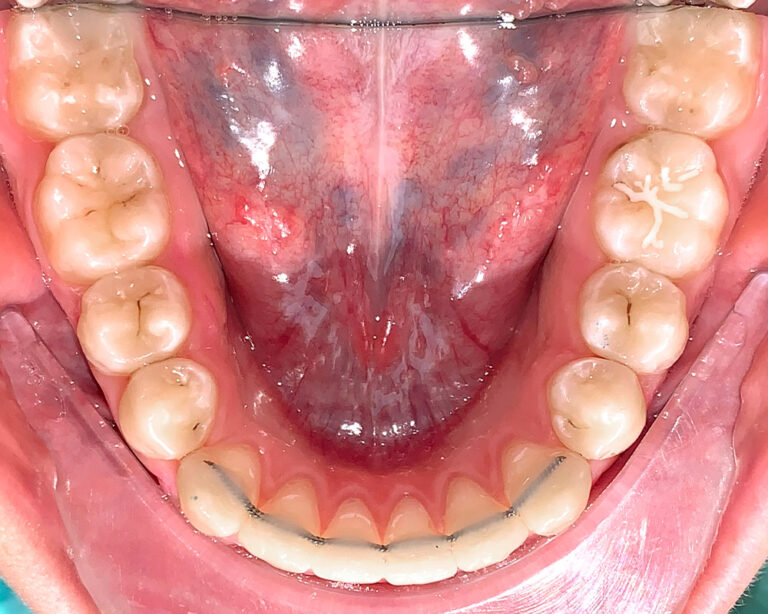

Кейс 16

Акинфиева

Количество кап ВЧ 20

Количество кап НЧ 20

ДО

ПОСЛЕ